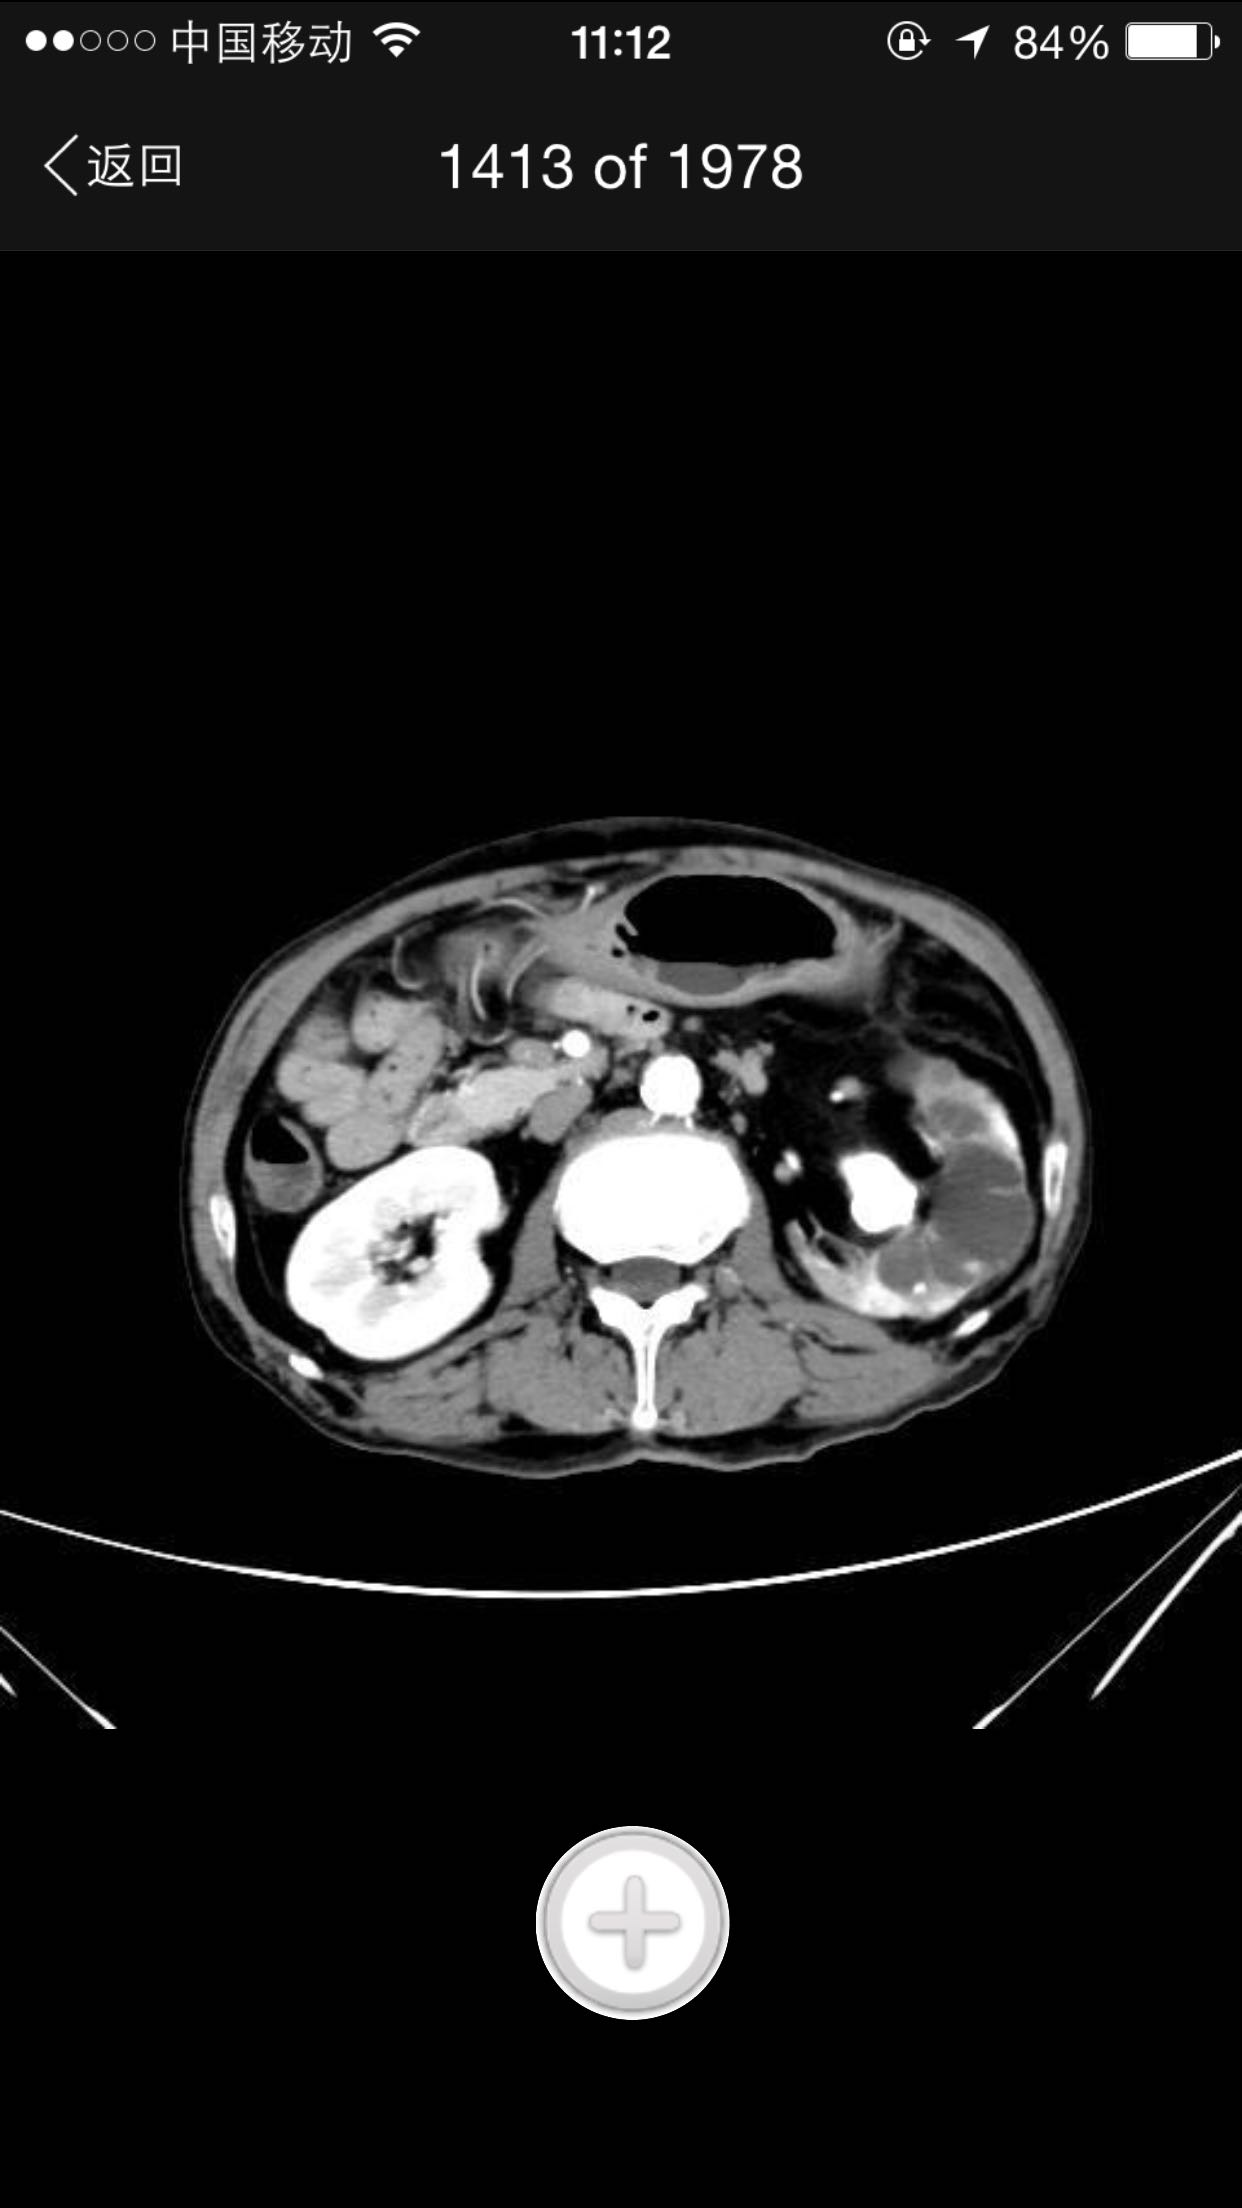

排尿困难,尿潴留入院。诊为前列腺增生症,拟行手术治疗。完善术前检查,泌尿系CT检查发现左肾占位,左肾结石并左肾重度积水,左肾萎缩等。既往患者肺结核病史,服药控制半年余。

查体:腹平软,无压痛及反跳痛,无肾区叩痛,肛诊前列腺明显增大,中央沟消失,无硬结,无压痛。术前强化CT提示左肾癌。

术前诊断:1、左肾癌2、左肾结石3、左肾积水4、左肾萎缩5、前列腺增生6、肺结核 入院后完善检查,拟行TURP,因发现左肾癌,改为先行肾手术。患者左肾癌,同时左肾结石,肾萎缩,决定行根治性肾切除,拟腹腔镜下手术,患者家属不同意,改开放手术,全麻下行根治性左肾切除。术后剖开标本如下图,肿瘤位于肾上极,中间黑色为结石。